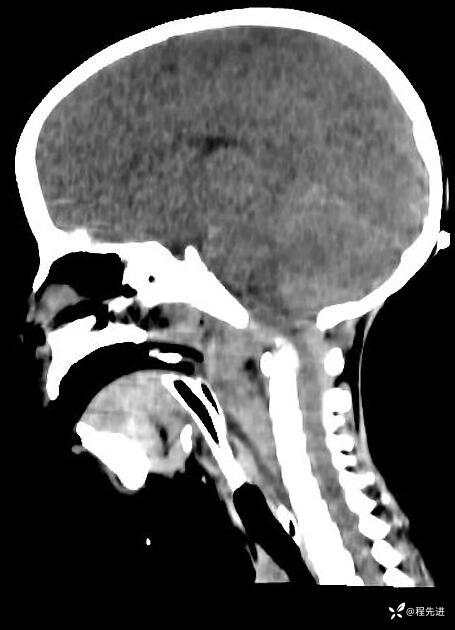

患者性别:男

患者年龄:5岁

简要病史:超速车祸外伤半小时

急诊CT平扫: